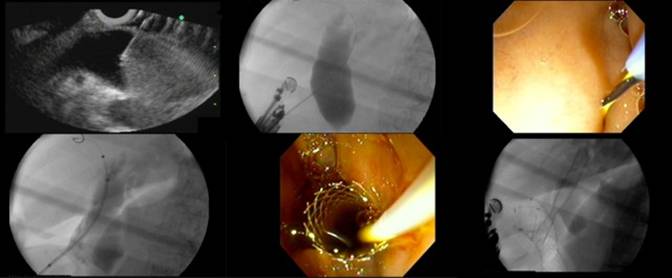

Two types of needle devices are available for access. Conducting flexible needles, commonly used at ERCP for pre-cut and pseudocyst drainage, using electrocautery (EndoCut ICC200, Erbe Elektromedizin GmbH, Tübingen, Germany). The so-called needle-knife (Zimmon papillotome, Cook Endoscopy, Winston-Salem, NC, USA), used for pre-cut, produces axial cutting with a thin wire extending 2 mm beyond the tip of the catheter. The so-called cystotome or fistulotome (Cook Endoscopy, Winston-Salem, NC, USA; Endoflex, Tubingen, Germany), traditionally used for pseudocyst drainage, has a blunt, round cutting piece at the tip that produces circumferential cutting. Cystotomes are slightly stiffer than needle-knifes and produce a larger burn on the duodenal and common bile duct walls. This larger, round cutting reduces the need for dilation before stent insertion. Therefore, cystotomes are particularly useful in cases where resistance to the advancement of flexible devices over the wire into the duct is met. Thinner caliber cystotomes (6 French) are preferable to larger caliber ones (10 French). On the other hand, needle-knives, being more flexible, can be used free hand under EUS as the initial access device. There are also non-conducting stiff cutting needles, commonly used for EUS-guided fine needle aspiration (EUS-FNA). EUS-FNA needles are available in several calibers. The two most commonly used are the large 19 gauge needle and the thin 22 gauge needle (EchoTip, Cook Endoscopy, Winston-Salem, NC, USA) (Figure 1). Whatever the needle choice, it is inserted transduodenally into the bile duct under EUS visualization. To confirm needle ductal access, the stylet is removed and bile is aspirated. If there is a bile return, contrast medium is injected into the bile duct for cholangiography, then, a 450 cm long, 0.035 inch, 0.021 inch, or 0.018 inch guidewire is inserted through the outer sheath and its position is confirmed fluoroscopically. We will comment below on differential guidewire features. If there is no return of bile or a bloody aspirate, the needle is removed, flushed with saline inside the gastrointestinal lumen to prevent clogging, and a repeat puncture attempted. Nonetheless, the problem of a needle apparently inside the duct under EUS but in actual fact on a different plane usually occurs when accessing very small ducts, which is hardly ever the case during EUS-guided choledochoduodenostomy. After guidewire access into the bile duct, some dilation of the puncture track is usually necessary, using either a dilating biliary catheter (Soehendra biliary dilator, Cook Endoscopy, Winston-Salem, NC, USA), a papillary balloon dilator (Maxpass, Olympus Medical Systems, Tokyo, Japan) or both sequentially (axial dilator first, then balloon dilator). This is aimed at dilating the duodenocholedochal fistula to facilitate stent insertion. The need for dilation is maximal when no cautery is used for initial entry under EUS, a stiffer (metal) or larger caliber plastic (10 French) stent is intended, and when the distance to the common bile duct or the resistance felt during the initial advancement of the needle are greater. Finally, a 5 to 10 French biliary pigtail or straight plastic stent or a fully covered self-expandable metal stent (Zeon Medical Co. Ltd., Tokyo, Japan) is inserted through the choledochoduodenostomy site into the common bile duct. Care should be taken to monitor by fluoroscopy the intraductal placement of the proximal end of the stent and to monitor by endoscopy the intraduodenal (or intragastric) position of the distal (closer to the scope) end of the stent. This latter aspect is of particular relevance when using self-expandable metal stent. Self-expandable metal stent tends to foreshorten upon full expansion, which takes place a few hours after the procedure. Early self-expandable metal stent dislodgment may be caused by foreshortening towards the common bile duct beyond the gastrointestinal wall. To prevent this serious complication an adequate length of self-expandable metal stent (15-20 mm) should be left inside the gastrointestinal lumen. This is longer than what is customarily done when placing self-expandable metal stent transpapillary at ERCP. Additional anchorage techniques to prevent dislodgment are forceful balloon dilation of the self-expandable metal stent up to 8-10 mm after initial deployment, or the use of a coaxial double pig-tail through the self-expandable metal stent, as reported for pseudocyst drainage using transmural self-expandable metal stent [19].

Figure 1. EUS-guided choledochoduodenostomy. It is demonstrated the step-by-step technique in which we can see the EUS images with the dilated common bile duct being punctured, cholangiography with guidewire placement, fistulization using a needle-knife catheter, deployment of partially covered self-expandable metal stent. |

Despite the seemingly simple sequence of duct imaging and puncture under EUS, guidewire advancement and track dilation under fluoroscopy, and eventually stent insertion and deployment under combined fluoroscopic and endoscopic monitoring, EUS-guided choledochoduodenostomy is an invasive, complex procedure. Knowledge about the full array of needle devices, guidewires, dilators and stents as well as about the subtle variations in scope position (gastric or duodenal), scope orientation (upward and downward), and stent anchoring techniques is highly recommended to increase success rates and minimize complications. Operator confidence with specific devices also plays a role. Some authors feel that access without cautery is less prone to complications. These authors favor initial non-conducting needle access and then use cautery only selectively after failed mechanical dilation over the guidewire of the puncture tract [6, 20]. Mechanical dilation without cautery requires a stiffer 0.035 inch guidewire for support, which in turn involves the use of a 19 gauge EUS-FNA needle. Other authors find the stiffer 19 gauge EUS-FNA needles cumbersome to use in the relatively long position of the echoendoscope in the duodenum, and resort to either initial direct needle-knife access under EUS [21], or needle-knife access under a thinner 0.018 guidewire passed into the common bile duct after puncture with a 22 gauge EUS-FNA needle [22]. Finally, some other authors resort to both needle-knife and EUS-FNA needle access [23].